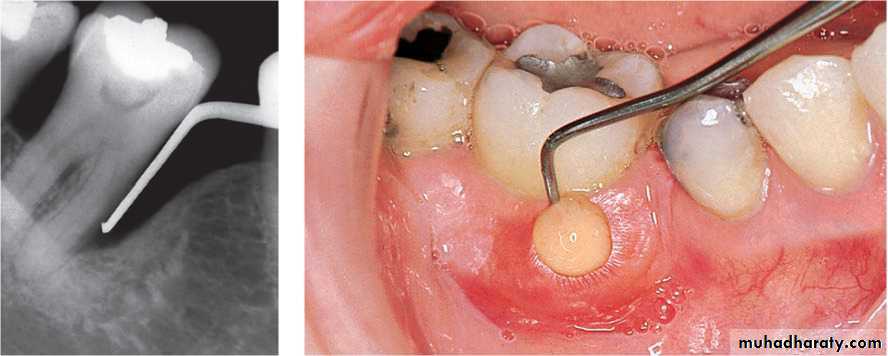

Cyst/osteosclerosis may present difficulties in planning shape of ridge.Special care of infective endocarditis/diabetes/coronary heart disease.

are:1.The teeth sit into sockets of the extracted teeth, gives more natural appearance2 .Esthetically good initially

(4) Insertion of the clear acrylic template to check if bone removal has been sufficient. Blanching of the mucosa is clearly seen beneath the template in any area where there is excessive pressure.

(5) Suturing of the sockets and insertion of the immediate denture.